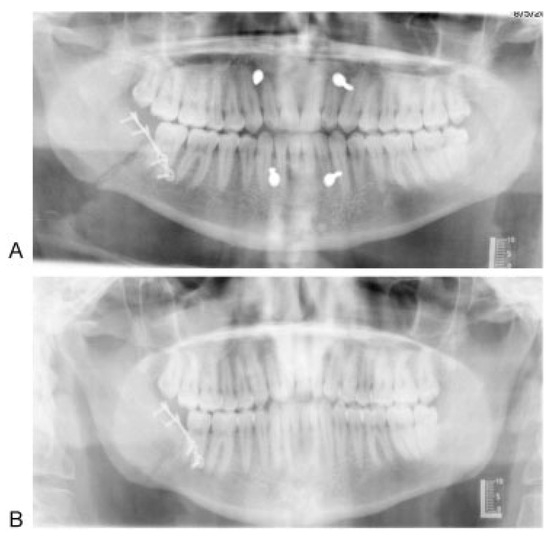

A Prospective Study of Strut Versus Miniplate for Fractures of Mandibular Angle